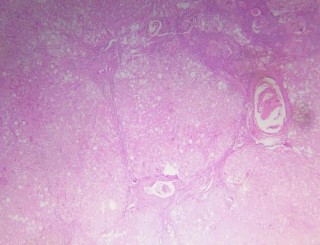

Hình 2.10. Tổn thương gan 4/6 theo Ishak (BN A10-0047088)